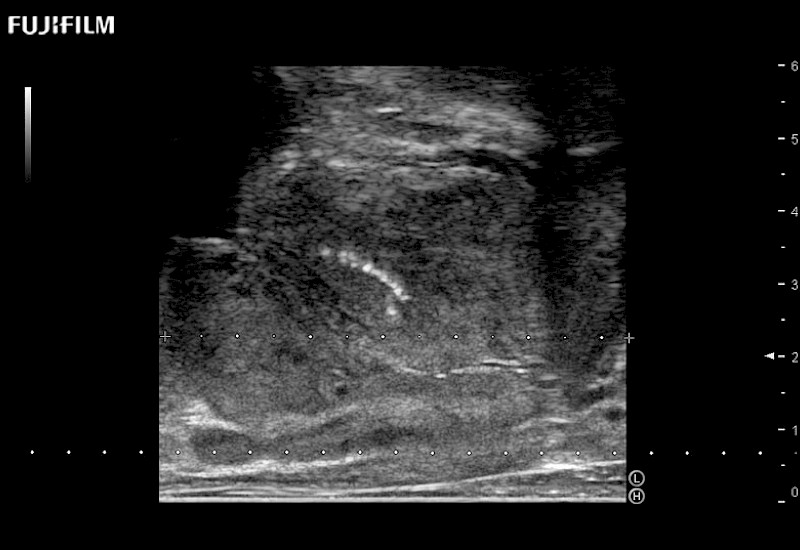

Ideal transducer for Transperineal Biopsy, Hydrogel Spacer Placement, Brachy LDR & HDR, Cryo, and MPMRI procedures.